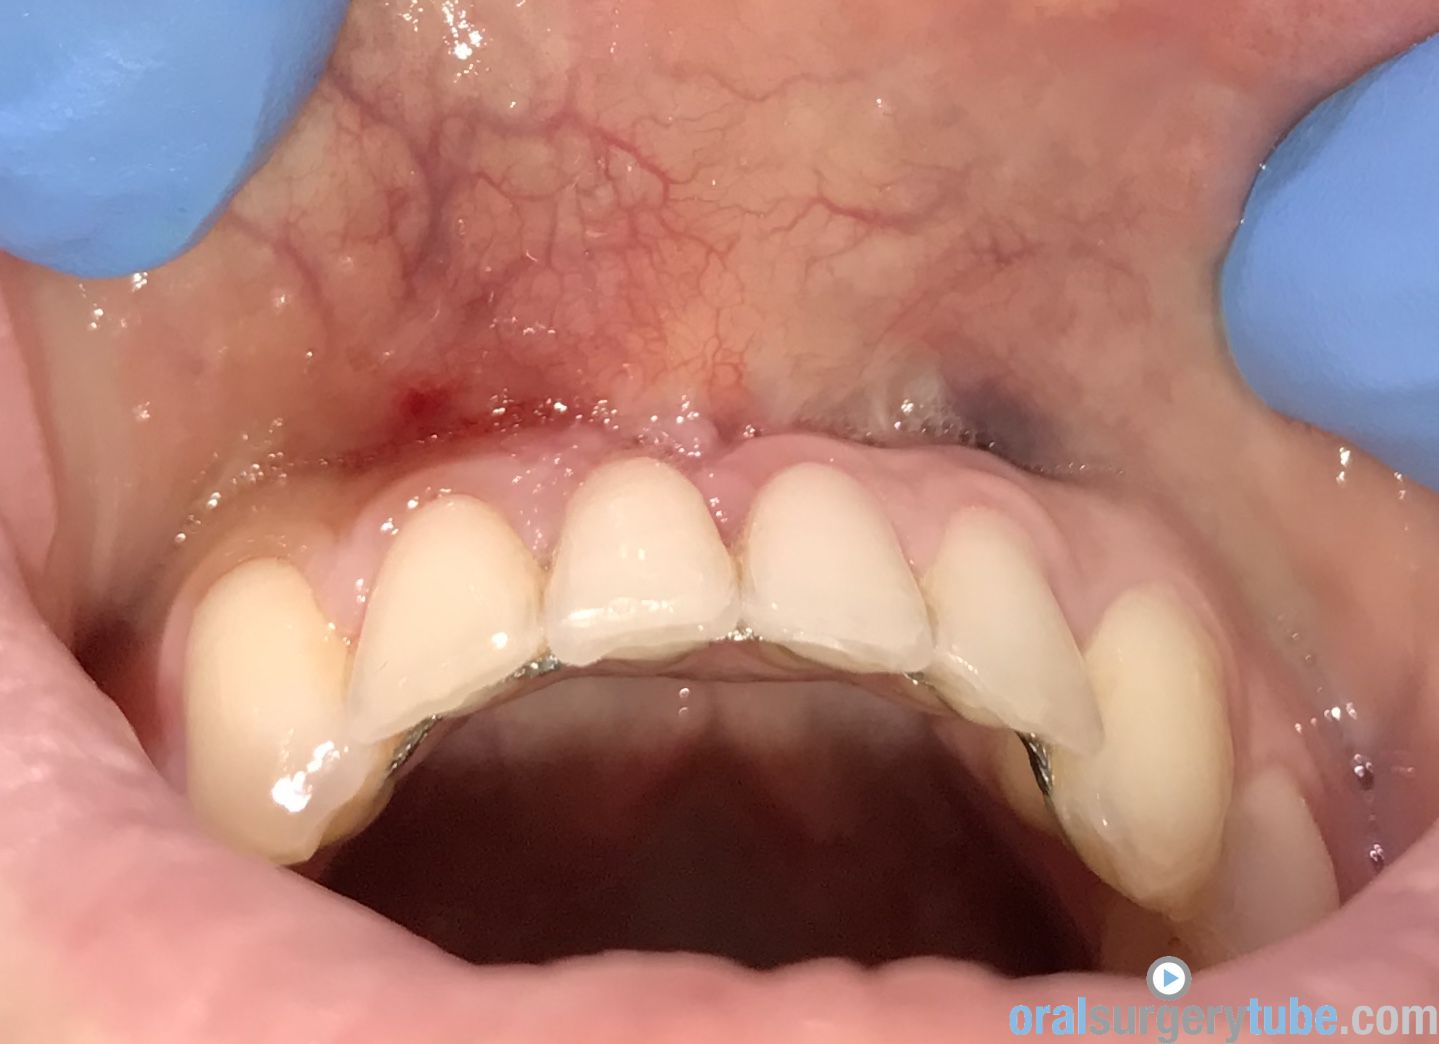

Paciente joven acude para consultar acerca de recesión gingival pieza 31 (clase II Miller). Paciente deja constancia de la importancia de la estética para ella. Hace unos 6 meses, se le realizó cirugía mucogingival con injerto conectivo palatino (la cuál fue fallida, ya que la recesión permanece)... Refiere además cierta molestia al traccionar del labio.

Al movilizar el labio, me transmite la sensación de haber quedado una inserción de fondo de vestíbulo alta... Pienso que podría ser debido a no haber realizado una desinserción muscular al reponer el colgajo coronalmente? (Foto 2). Considero que aún mantiene cierta cantidad de banda queratinizada, pero realmente mínima.

Dado a que se trataría de realizar una "reentrada" o retratamiento (no tengo experiencia hasta la fecha de haber tenido que retratar ningún caso de mucoginigval), agradecería toda opinión acerca de la técnica que más idónea consideréis... Teniendo en cuenta esas posibles adherencias musculares, el biotipo, la demanda estética de la paciente, no sé si lo ideal es tratar con injerto conectivo tipo "técnica bilaminar" y desinsertar la musculatura, o un Injerto de Encía Libre (FGG) y reponer apicalmente la musculatura...

La duda que me surge con el injerto conectivo es si el colgajo me permitiría ser reposicionado coronalmente, teniendo en cuenta esa sensación de "tirantez" actual que describe el paciente. Y la duda de realizarlo con FGG es si conseguiría cubrir la recesión por completo, y si es adecuado para ese solo diente...